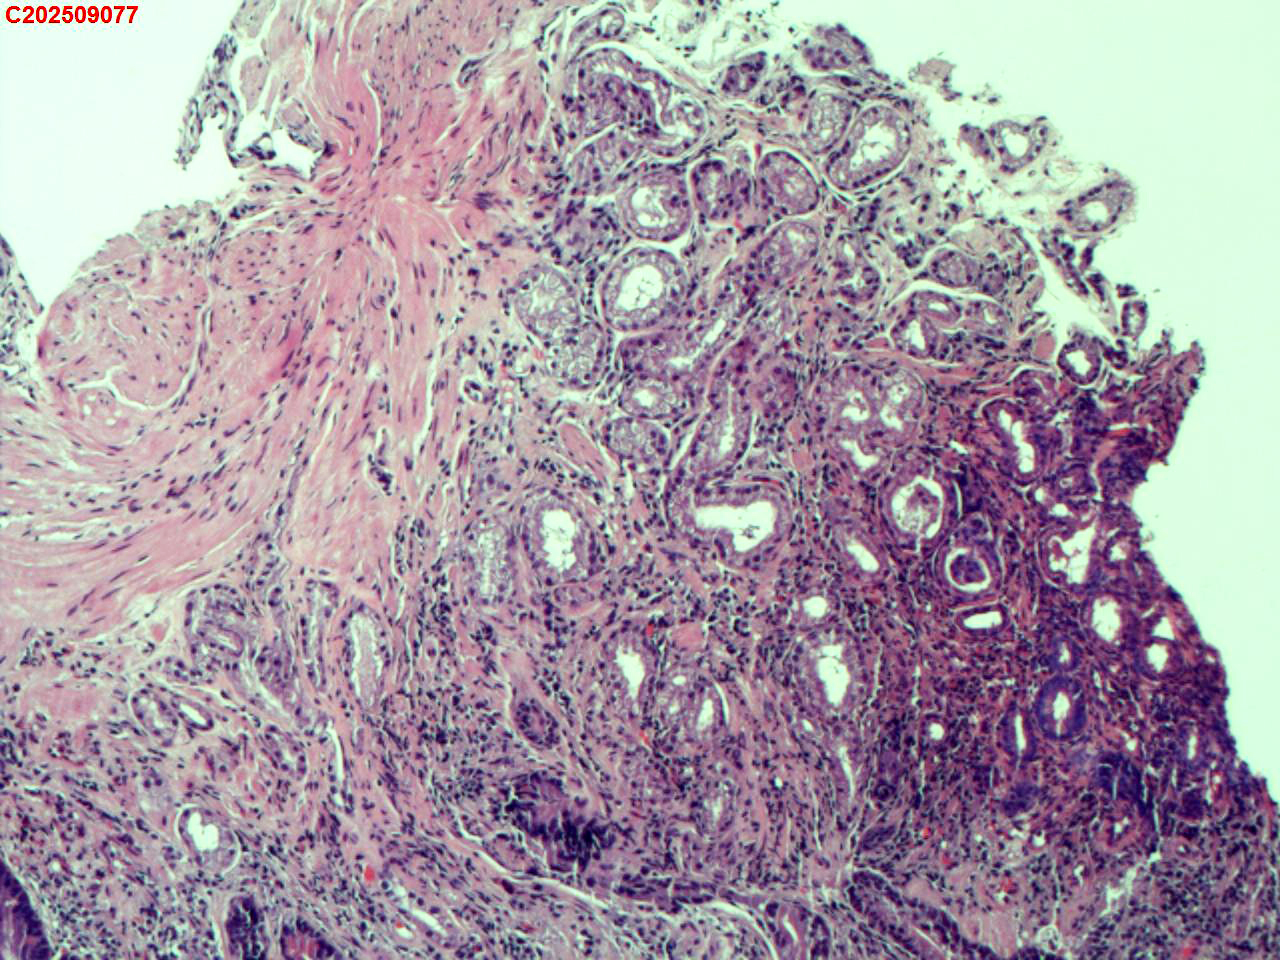

胃角粘膜

性别

男

年龄

65岁

临床诊断

胃炎伴糜烂

一般病史

体检

标本名称

大体所见

胃角多发片状充血、糜烂

图1

萎缩+肠化+修复。